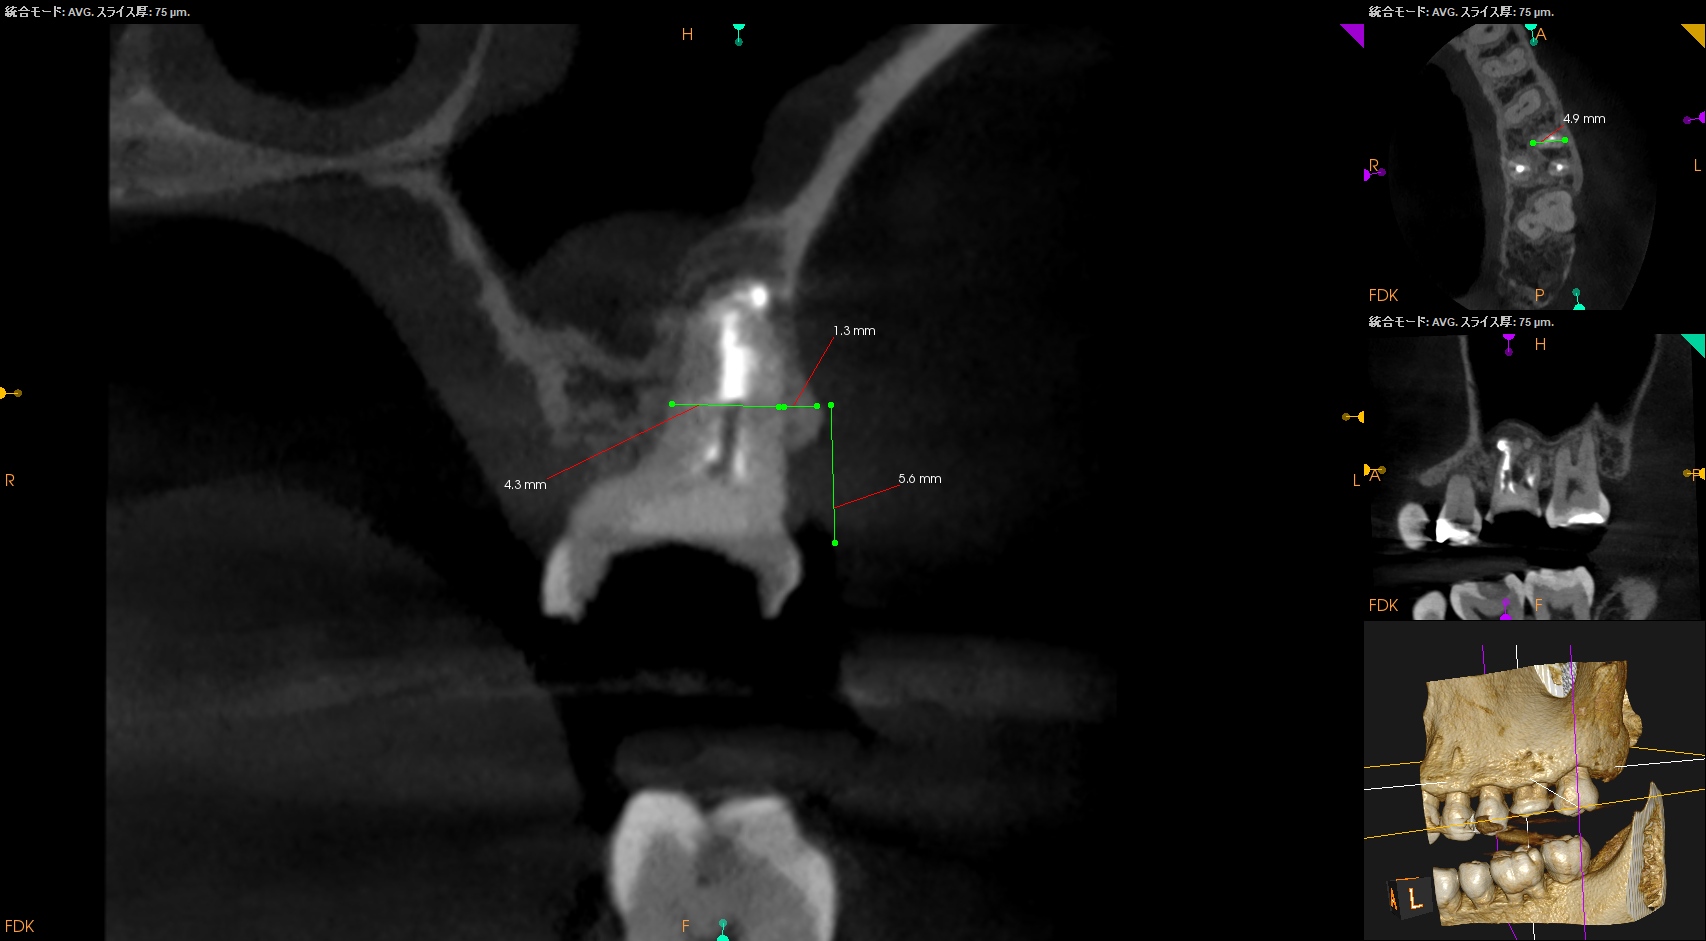

さて、外科の際は

上顎洞の穿孔を避けるため、MBはCEJよりも5.6mm下方に1.3mm Osteotomyして頬舌的に4.3〜4.9mm切断する必要がある。

これはそれほど困難ではない。

その後、Root tipごと取り出す形になるだろう。